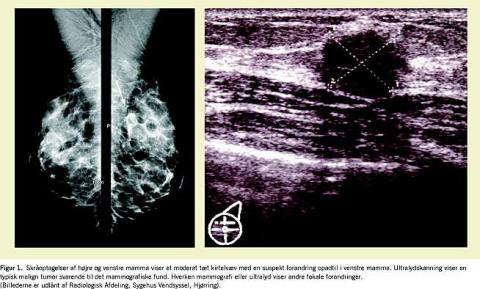

I en række undersøgelser har man påvist, at MR generelt har en meget høj sensitivitet, i nogle opgørelser op til 100%, mens man i de samme undersøgelser har fundet vekslende specificitet. Falsk positive resultater forekommer, og undersøgelsen skal indpasses i kvindens cyklus. Undersøgelsen bør derfor fortsat betragtes som et supplement til mammografi og ultralyd (Figur 1 og Figur 2 ).

Indikationerne for MR-mammografi er ikke endeligt fastlagt, men indikationer for MR-mammografi kan være mistanke om implantatruptur, hvis ultralyd er usikker, og undersøgelse forud for planlagt lumpektomi [10]. Her synes brug af præoperativ MR at medføre færre recidiver i det opererede bryst. Andre indikationer kan være uafklarede fund ved mammografi og ultralydskanning og på det seneste screening af unge kvinder, der er i højrisikogruppe med påvist sygdomsgivende BRCA1- eller BRCA2-genmutation og ved stærk familiær disposition.